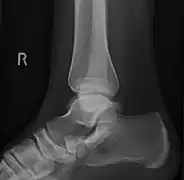

Radiological images

Cornuate navicular bone